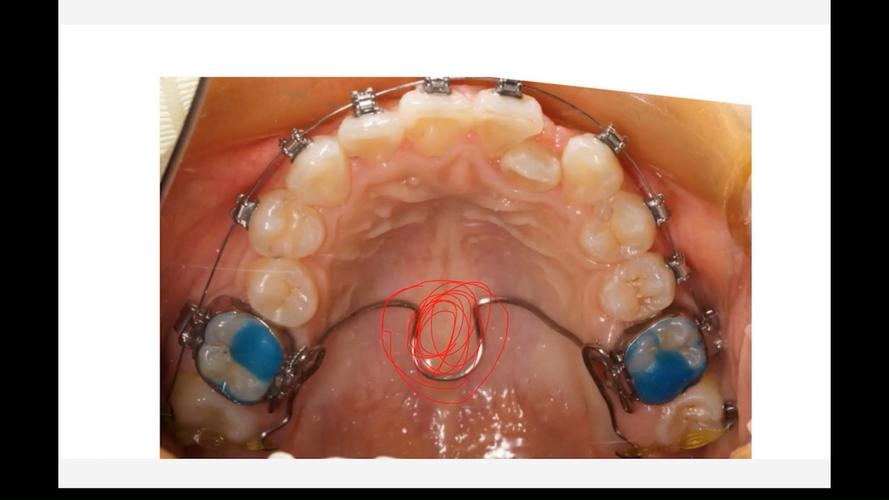

Damon系统的核心突破在于“自锁托槽”结构和“生物力学轻力”理念,传统托槽依赖结扎丝或橡皮圈固定弓丝,弓丝与托槽间摩擦力较大,牙齿移动需较大力量且速度较慢;而Damon托槽通过内置的滑盖或锁片结构,将弓丝直接“锁”在托槽槽沟内,无需结扎,弓丝可在槽沟内自由滑动,这种设计大幅降低了牙齿移动时的摩擦力(摩擦力仅为传统托槽的1/5-1/3),使牙齿在持续、轻柔的生物力作用下实现高效移动,同时减少对牙周组织的刺激。

- 粘接托槽:清洁牙齿酸蚀后,将Damon托槽精准粘接在牙面,安装初始镍钛弓丝,开始轻力移动牙齿。

- 复诊调整:每6-8周复诊一次,医生更换更粗的弓丝或调整托槽位置,持续引导牙齿移动。